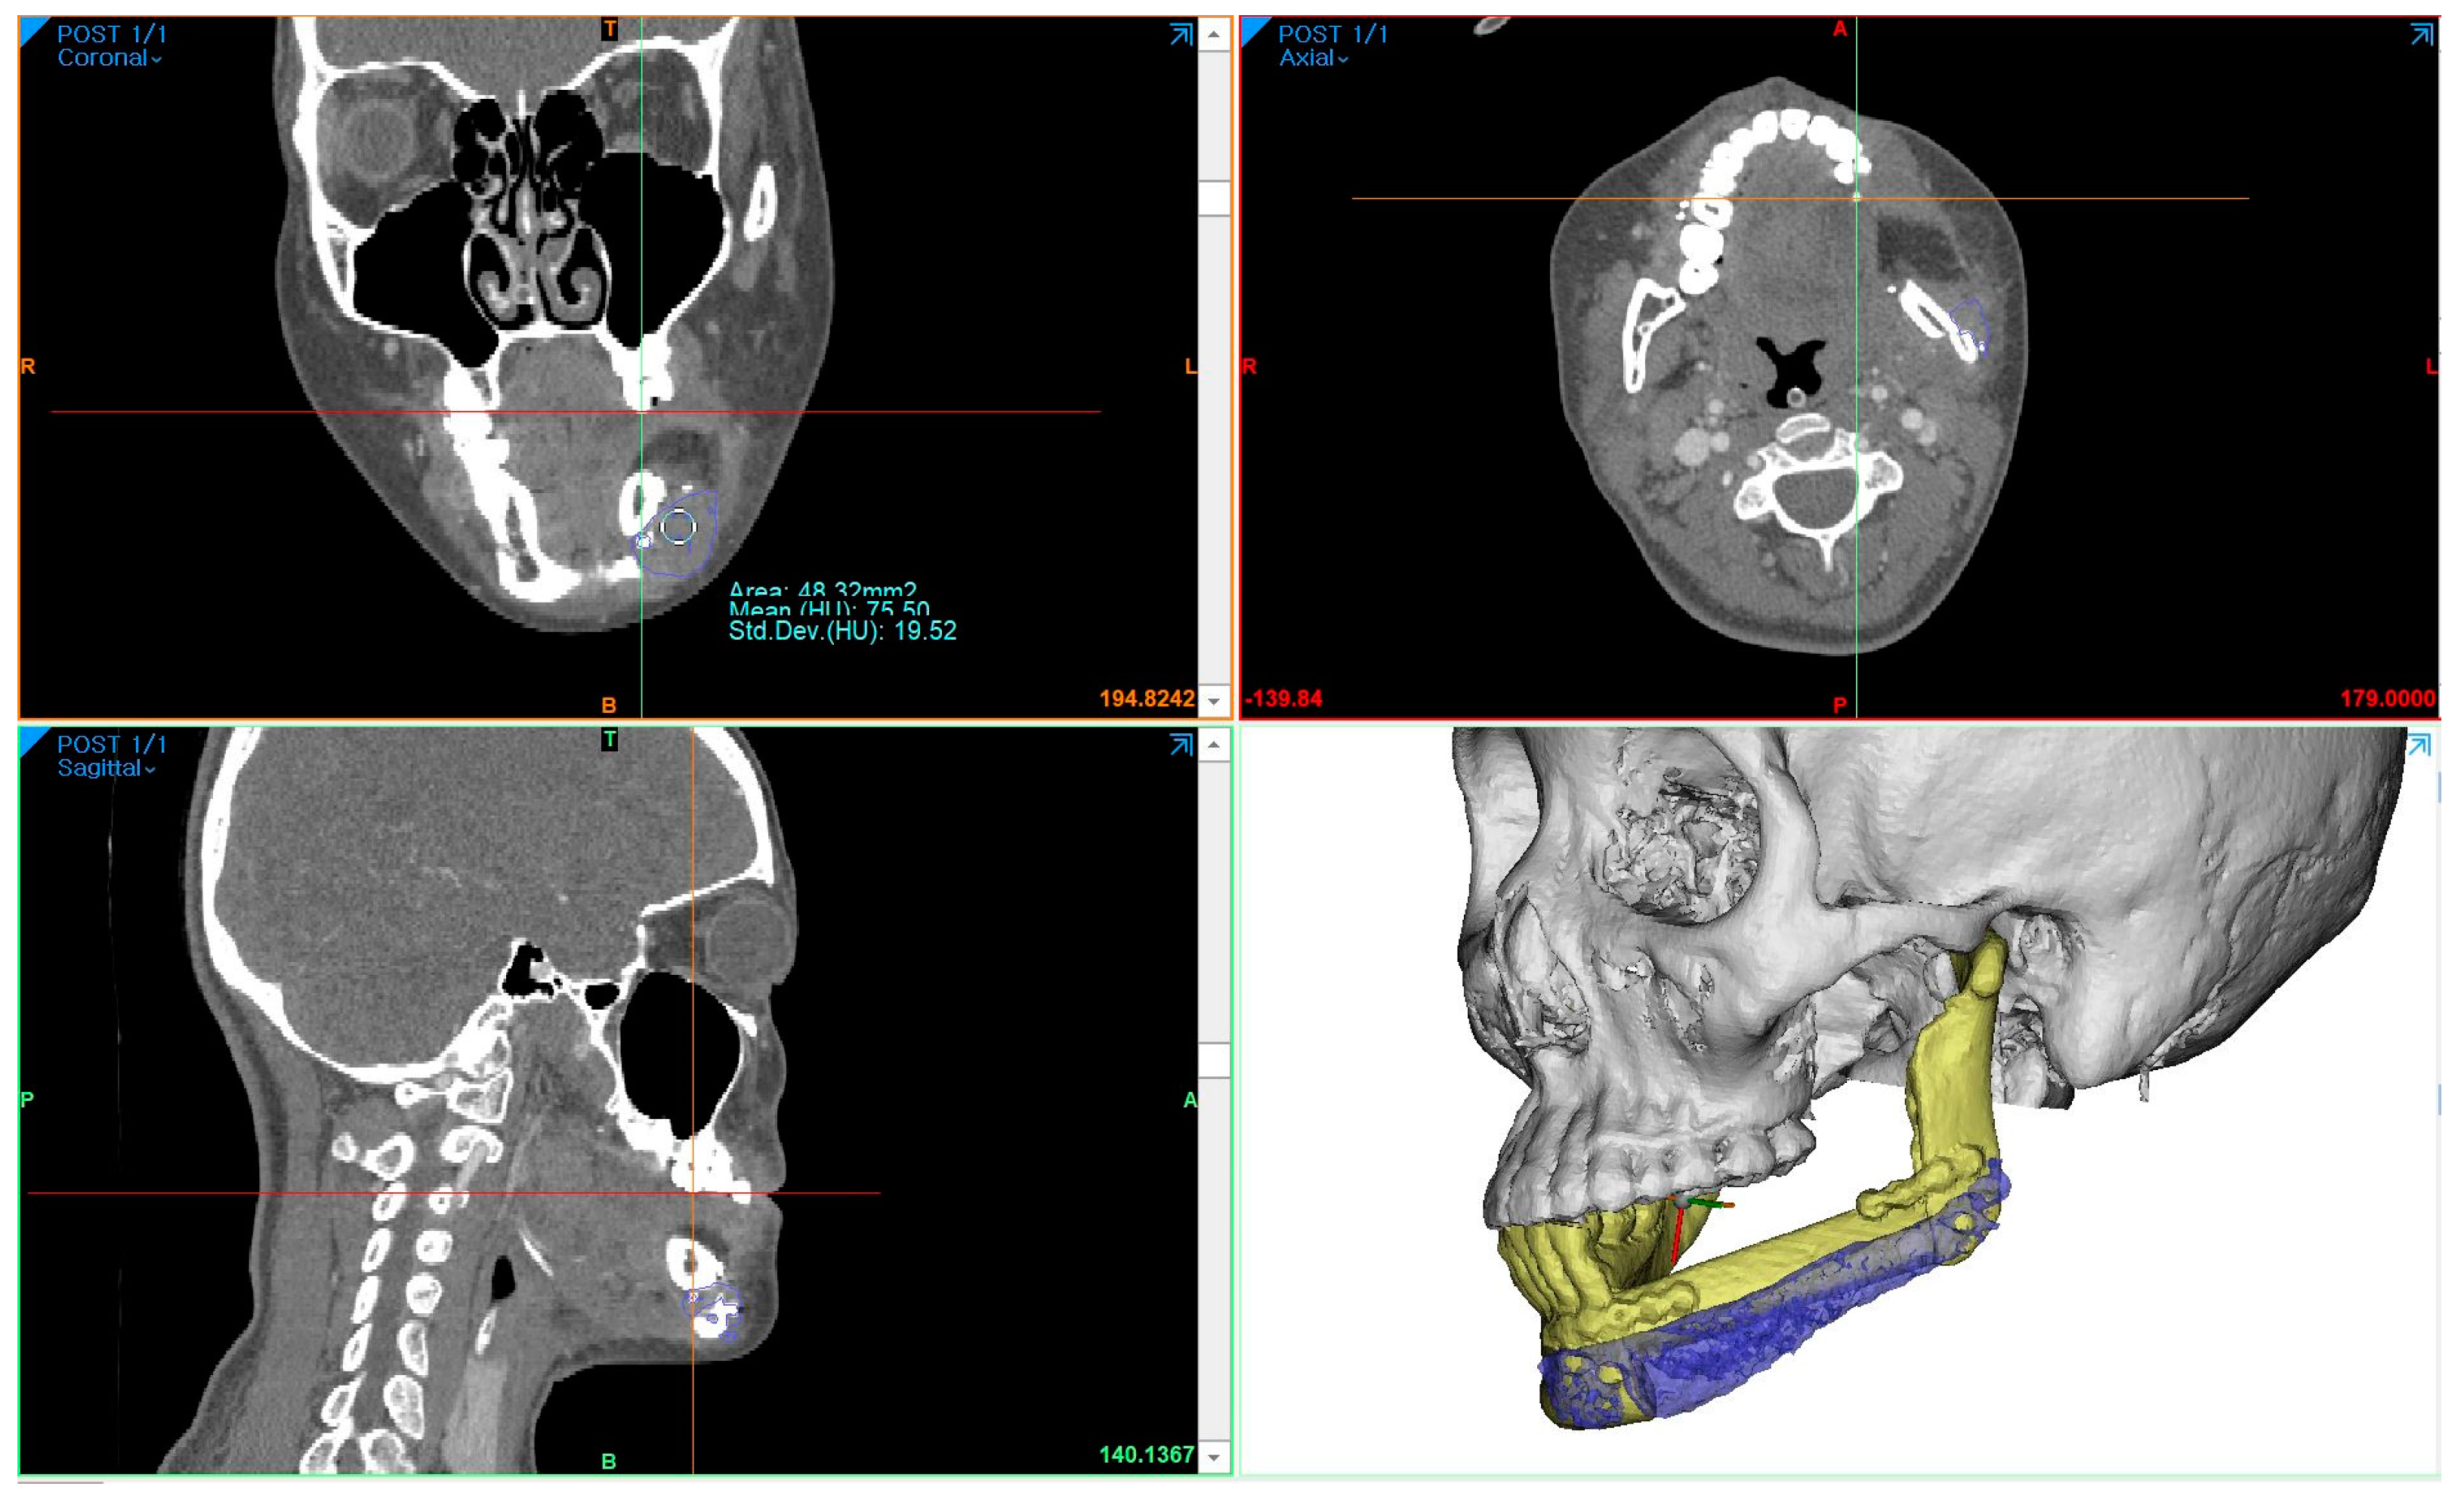

To measure the density of the PCL implant using follow-up-enhanced CT and Mimics software, the same location where the PCL was positioned at the level of the maxillary first molar was identified in the coronal view. At this specific location, the mean value and standard deviation of the Hounsfield units (HUs) were obtained using the “density” function (Figure 5). To compare accuracy on the same software, 3D models of surgical planning and the 3D model generated from the CT data taken two weeks after the operation were superimposed, and the error was calculated through mapping analysis.

The surgical results were analyzed using enhanced CT and MRI, which were radiographic images taken for the purpose of tracking malignant tumors. Follow-up CT scans were conducted at 2 weeks postoperatively and every year for the next 6 years, whereas MRI scans were performed only at 5 months, 11 months, 40 months, and 4-and-a-half years after surgery. The PCL implant exhibited similar attenuation to the surrounding soft tissue on the enhanced CT images, making it challenging to accurately generate a 3D model rendering in the Mimics software. The Hounsfield unit value of the PCL implant was measured using the “density” function in this software. It was observed that the density progressively increased over the years, from 75.50 at 2 weeks after surgery to 107.69 at 6 years after surgery (Figure 6). All average values were within the range of muscle thresholds. On the follow-up MRI, the PCL implant exhibited signals between the surrounding soft tissue and hard tissue, allowing for clear margin distinction. Consequently, changes in volume could be observed on the MRI, and there were no significant changes until 4-and-a-half years after surgery. The lattice pattern of the PCL, which was clearly observed until the 11-month postoperative MRI image, was absent in the 40-month postoperative MRI image, and it was analyzed that only the surface of the PCL had been replaced with soft tissue (Figure 7A,B). By superimposing the model immediately after surgery with the virtual plan, it was determined that the error was within 1 mm, except for the condylar head (Figure 7E).

Figure 5. Using the “density” function in Mimics software, the Hounsfield units’ value of the PCL implant area was obtained at the same location. In this case, the measurement of the same region was conducted at the level determined by the location of the hemoclip below the fibula segment and the maxillary first molar in the CT coronal view.